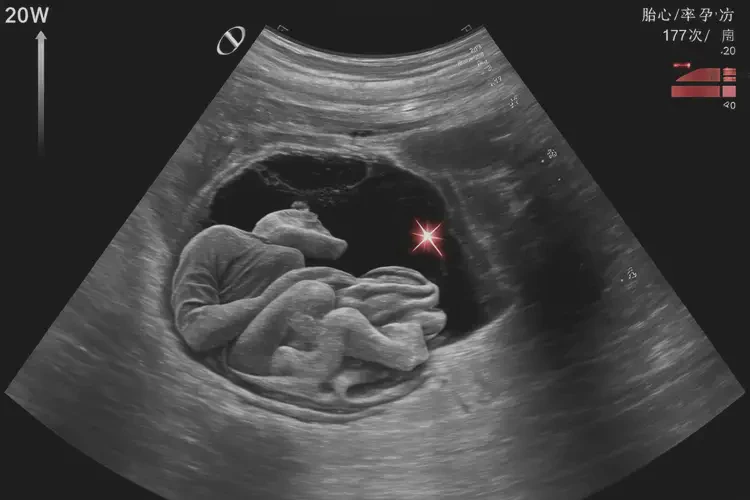

胎心率177次/分钟在孕20周1天时属于正常范围,通常无需特殊保胎措施。

胎心率是指胎儿心脏每分钟跳动的次数,是评估胎儿健康状况的重要指标之一。在孕20周左右,胎儿的胎心率通常在120-180次/分钟之间波动。胎心率为177次/分钟虽然接近上限,但仍在正常范围内。

- 孕中期(12-28周):胎心率通常在120-180次/分钟之间。

胎心率监测是产前检查中的重要环节,可以帮助医生及时发现胎儿的异常情况,并采取相应的处理措施。孕妇应该定期进行产前检查,包括胎心率监测,以确保胎儿的健康发育。

通过以上分析,我们可以得出结论:胎心率177次/分钟在孕20周1天时属于正常范围,通常无需特殊保胎措施。但如果胎心率持续异常或波动过大,应及时就医咨询专业医生的意见。孕妇应该定期进行产前检查,包括胎心率监测,以确保胎儿的健康发育。